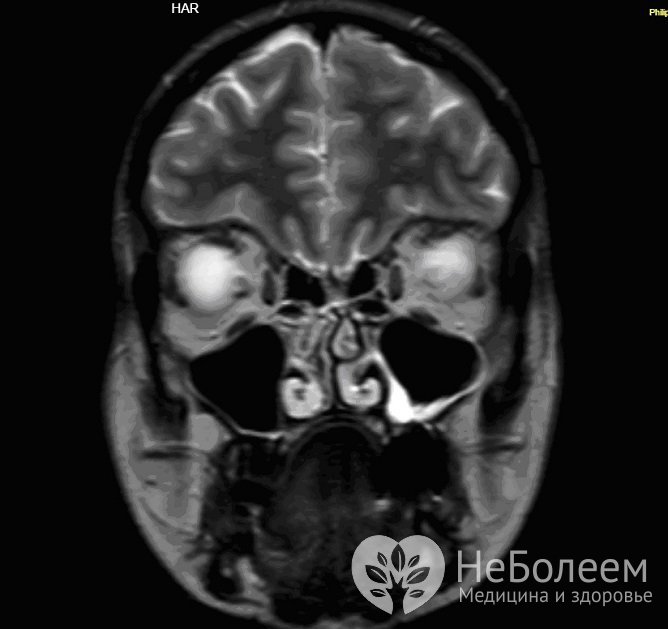

Для уточнения диагноза может быть назначена магнитно-резонансная томография гайморовых пазухОсобую информационную ценность в распознавании патологии гайморитов представляет эндоскопическое исследование синуса, а также КТ и МРТ (компьютерная и магнитно-резонансная томография). С помощью КТ удается точно определить характер и распространенность патологического процесса, степень вовлечения костных и мягких тканей пограничных областей.